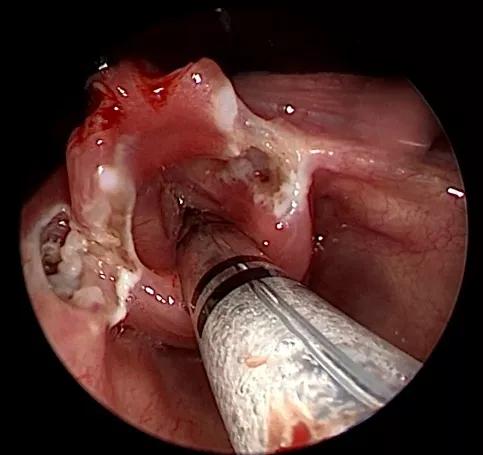

手术难度极高,颖颖是早产儿,手术时纠正月龄才一个月,喉部的空间极小,医生要利用低温等离子射频消融系统在喉显微镜下行声门上成型术,去除软化肥厚的粘膜,解除对气管的阻塞,帮孩子打通被堵塞的气道。

但是不能去除过多,否则会损害、刺穿孩子稀薄的气管,引起误吸,所以分寸的把握也是考验术者的难点。宛若在鹌鹑蛋里做微雕,饶是积累了十多年先天喉软化治疗经验的刘大波团队,也不敢掉以轻心。

▲(术中操作空间极小,手术难度大)